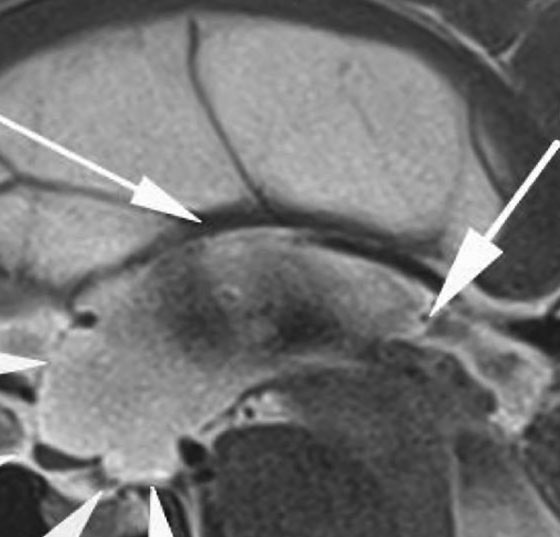

• Hydrocephalus occlusus bei proximaler Aquäduktstenose

Neuroradiologische Zeichen und neurochirurgische Behandlung

Fallbeschreibung: Wir berichten über einen 43-jährigen Patienten, der im Sommer letzten Jahres einen erstmaligen Krampfanfall erlitten hatte. Die umfangreiche Epilepsieabklärung ergab keine epilepsietypischen Potenziale. Im Rahmen der weiteren Abklärung zeigte...…